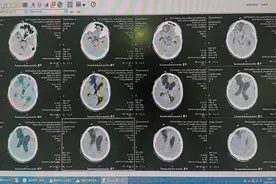

近日,滕州市中心人民医院神经外科一病区再次成功为一名重型颅脑损伤术后去骨瓣减压患者实施“改良颞肌重建+颅骨缺损修补术”。患者,男,52岁,因“开颅术后颅骨缺损3月余”来院就诊,CT提示“右侧额颞部分颅骨缺损、脑外伤术后改变”,以“右侧额颞部分颅骨缺损、脑外伤术后恢复期”收入院。